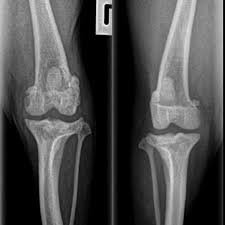

Bone cancer in dogs has been on a high in recent times because of the lack of awareness among dog owners regarding the provision of proper treatment most of the time, bone cancer in dogs is often mistaken for the sprain, patella luxation, hip dysplasia, arthritis, and other orthopedic disorders and is. 85% of bone cancer in dogs is a form called osteosarcoma. Bone cancer in dogs is rather common, with osteosarcoma as the most common type of bone tumor. In fact, noncancerous bone tumors are much more common than cancerous ones. Diagnosis of arthritis in dogs. That's why it's so important to be able to recognize the signs and seek. A systematic review of clinical trials. Stomach cancer and stomach ulcers both are digestive diseases. Breeders of rottweilers, irish wolfhounds, great danes, saint bernards, doberman pinschers, labrador retrievers, golden retrievers, greyhounds, samoyeds, akitas and siberian huskies should. Diagnosing bone cancer in dogs. Cancers that start in the bone marrow are not considered bone cancers. Stomach ulcer symptoms and signs differences quick view. Elderly people with conditions such as arthritis are especially vulnerable.

There is less cushioning and lubrication, and infectious arthritis can develop in dogs of any age. Osteosarcoma is less common in cats. Bone cancer most commonly affects the long bones in the arms and legs. Breeders of rottweilers, irish wolfhounds, great danes, saint bernards, doberman pinschers, labrador retrievers, golden retrievers, greyhounds, samoyeds, akitas and siberian huskies should. Helping your arthritic dog manage this inflammatory disease arthritis is a disease which affects many dogs. Neurological problems in older dogs. Risk of infections in rheumatoid arthritis patients treated with tocilizumab. Diagnosis of arthritis in dogs. Bone cancer in dogs what you need to know about osteosarcoma (part 1) vlog 71. Nancy reese for information on how to in september, 2008, north carolina state university announced that they are now offering bone marrow. In fact, noncancerous bone tumors are much more common than cancerous ones. Bile acids as carcinogens in human gastrointestinal cancers. Bone cancer in dogs is rather common, with osteosarcoma as the most common type of bone tumor.